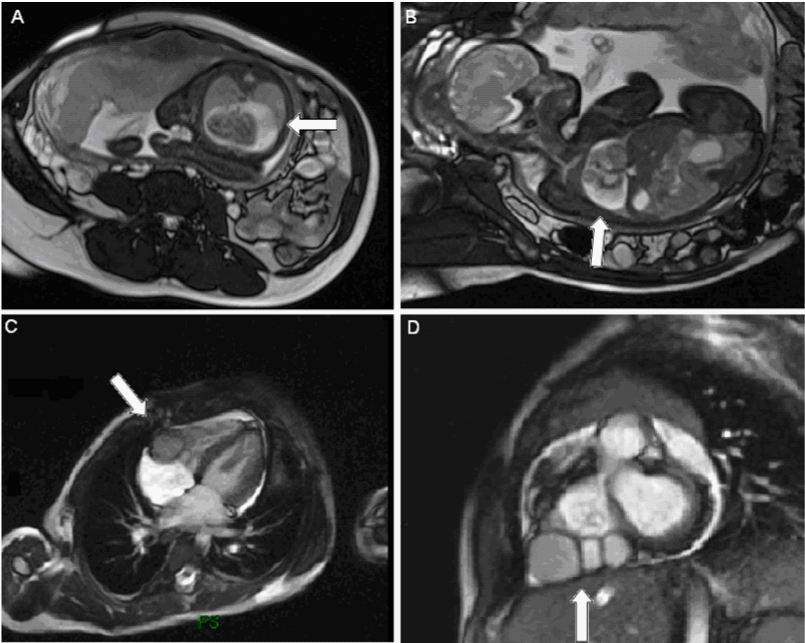

Figure 2 MRI Imaging Fetal MRI (A,B) in which is visible a large amount of pericardial effusion rounding the heart at the rear wall of left ventricle, compressing both lungs and showing pulmonary hypoplasia. Neonatal MRI (C,D) showing the multilocular diverticulum on the right ventricular free wall and the resolution of pericardial effusion.

As a consequence of this finding, serial echocardiograms for the evaluation of pericardial effusion, ventricular diverticulum size and fetal cardiac frequency were performed. It was shown a progressive increase of the amount of pericardial effusion and few episodes of fetal bradycardia, but no other structural abnormalities were identified. There was no evidence of maternal or fetal infection. At 32+2 weeks of gestation the patient underwent fetal cardiac magnetic resonance imaging (MRI) consisting of a static phase with multiplanar SSFP sequences and dynamic phase with real time SSFP sequences. Magnetic resonance imaging showed a large pericardial effusion of 13 mm at the rear wall of the left ventricle, with an outpouching measuring 15 mm x 10 mm developed on the right ventricular free wall, compatible with a right ventricular diverticulum (Figure 2). Both lungs were compressed with a normal regular intensity. In consideration of this pattern we decided to administer systemic corticosteroids to induce lung maturation. In delivery room, while emergency caesarean section was performed at 33+3 weeks of gestation, as a consequence of signs of fetal bradycardia, both cardiologist and cardiac surgeon were present. The mother delivered a live male infant in good conditions, weighing 1.880 Kg, with a 1 and 5 minute Apgar score of 8-9 respectively.

Among the therapeutic options, fetal pericardiocentesis has been suggested as a means of decompressing the fetal thorax, allowing reexpansion of the lungs and reduction in systemic venous pressure, leading to a theoretical reduction in the risk of pulmonary hypoplasia and hydrops in the fetus.1,5,8 We could have drained the pericardium during the antenatal period to improve lung maturation, but the risk was considered too high and therefore not worthwhile. Pulmonary hypoplasia completely resolved, managed only with corticosteroid therapy. In consideration of the hemodynamic stability, despite the amount of fluid, we decided to be conservative and not to drain. At the end we can say that was wise to wait and see because pericardial effusion disappeared progressively (Figure 2).